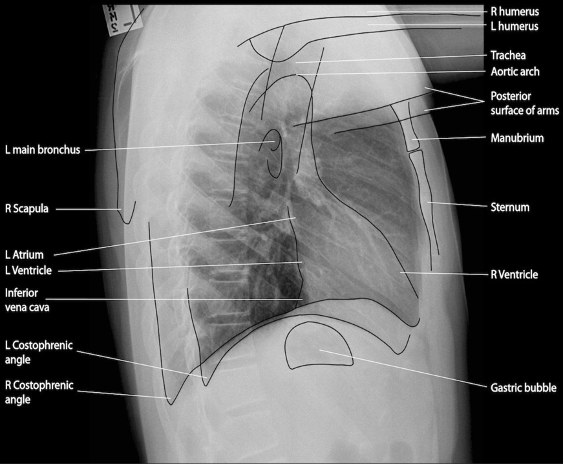

Normal rtg. af thorax:

- Lateral: